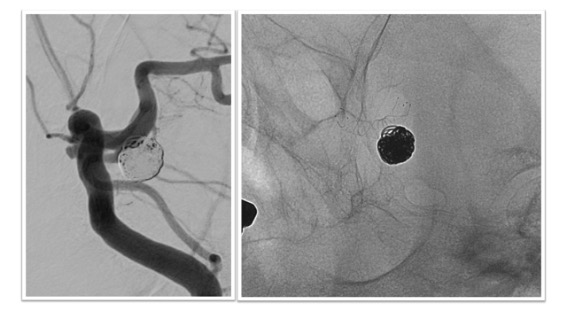

ステント併用コイル塞栓術治療実例(*患者様の許可を得て掲載しています)

内頸動脈後交通動脈分岐部(ICPC)動脈瘤

ICPCの動脈瘤へのステント併用コイル塞栓術後の脳血管撮影画像とレントゲンです。血管撮影画像から脳血管ステントを併用することで動脈瘤が塞栓され、動脈瘤から分枝している後交通動脈の血流は温存されている様子がわかります(図左 血管撮影)。内頸動脈で展開されたステントが壁となることで動脈瘤に充填された塞栓用コイルが内頸動脈や後交通動脈側にはみ出さぬようになっています(図右 レントゲン)。